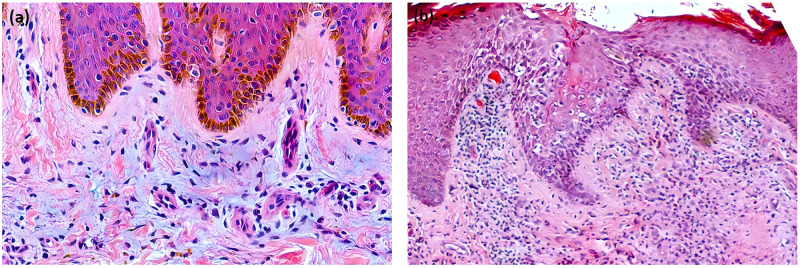

65岁亚洲男性,右小腿屈肌侧出现圆形皮肤病变,首次出现于13岁,并逐渐向周围扩展。在发病前6个月,环状病变上出现深棕色角状角膜病变,质地坚硬,逐渐生长,无疼痛或瘙痒。手术切除皮角,并对环形病变进行活检。病理结果显示真皮胶原蛋白中有丰富的粘蛋白,致密的组织细胞浸润,局灶性轻度胶原变性,确认诊断为环形肉芽肿合并皮角。

A 65-year-old Asian male presented with a circular skin lesion on the flexor aspect of the right calf that first appeared at age 13 and gradually expanded peripherally. Six months prior to presentation, a dark brown, horn-like keratotic lesion with a hard texture emerged on the annular lesion, growing progressively without pain or pruritus. The cutaneous horn was surgically excised, and the annular lesion underwent biopsy. Pathological findings revealed abundant mucin in dermal collagen, dense histiocyte infiltration, and focal mild collagen degeneration, confirming a diagnosis of granuloma annulare complicated by a cutaneous horn.